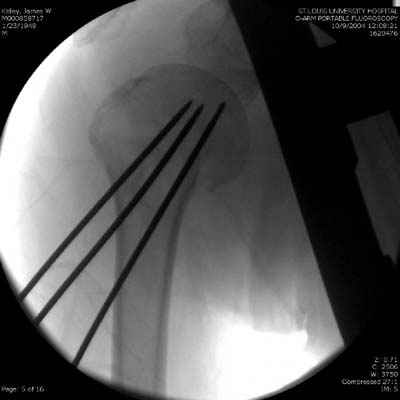

Сегодня взял больного повторно в операционную, не скажу, что повторная репозиция через неделю после первой попытки, была простая.

После удаления спиц попытался манипулировать отломками, но безуспешно, поэтому пришлось пользоваться периостальным элеватором, чтобы устранить смещение отломков и перепровести спицы. Проверил и перепроверил стабильность фиксации под ЭОПом, завтра Рг- будет готов, вот и поглядим....

Что-то, наверно, сделали мы не совсем оптимально, поскольку у Анатолия Федровича и его соратников как-то красивее "раскрываются" спицы в головке плеча - надеюсь, он прокомментирует и подскажет, что надо подправить.